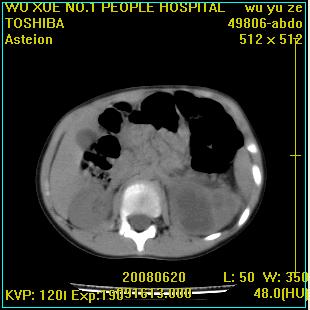

标题: PED0851:患儿,7岁,左腰部外伤一天,伴大量肉眼血尿。 [打印本页]

标题: PED0851:患儿,7岁,左腰部外伤一天,伴大量肉眼血尿。

左甚积液,输尿管近端扩张,考虑输尿管中下段梗阻

左输尿管上段梗阻伴左肾盂肾盏扩张积液

左肾积液,输尿管近端扩张,考虑输尿管中下段梗阻  ,左肾结核?

1 肾盂输尿管交界处狭窄

2 囊性肾发育不全

左肾积液,上段输尿管扩张。

左侧输尿管中段狭窄伴输尿管肾积水,考虑先天性狭窄可能性大.

左肾重度积水,原因不明;不排除左输尿管上段迷走血压迫或先天性狭窄所致可能。